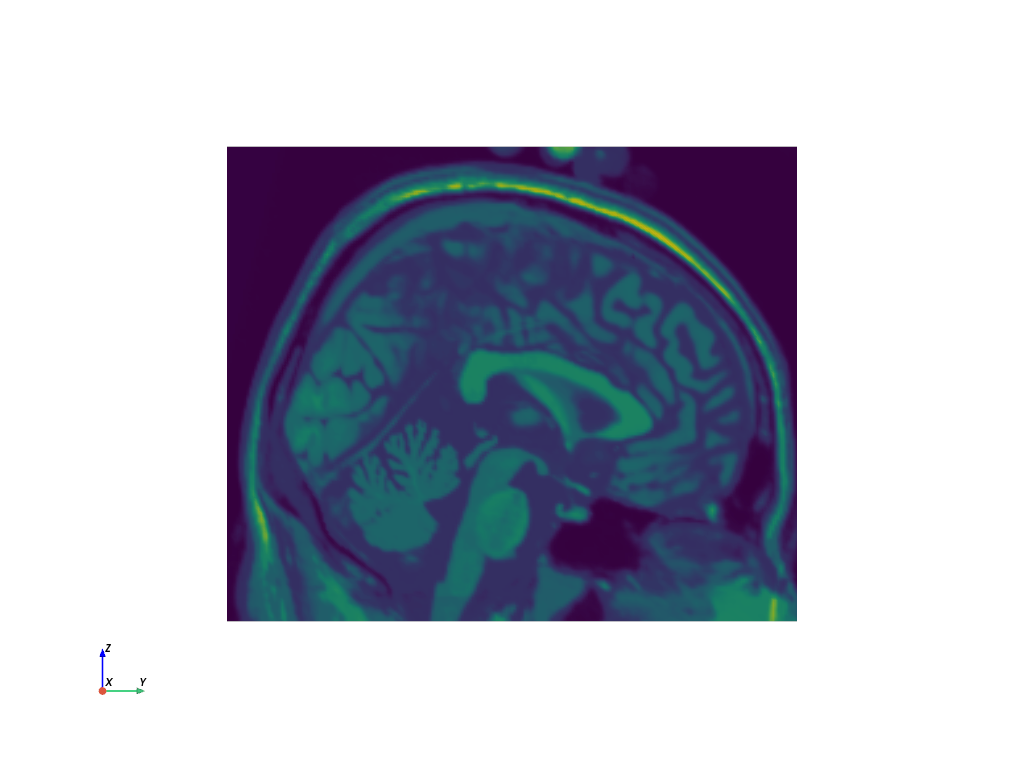

>>> import pyvista as pv

>>> from pyvista import examples

>>> filename = examples.download_brain(load=False)

>>> filename.split("/")[-1]  # omit the path

'brain.vtk'

>>> reader = pv.get_reader(filename)

>>> mesh = reader.read()

>>> sliced_mesh = mesh.slice('x')

>>> sliced_mesh.plot(cpos='yz', show_scalar_bar=False)

../../../_images/pyvista-VTKDataSetReader-1_00_00.png